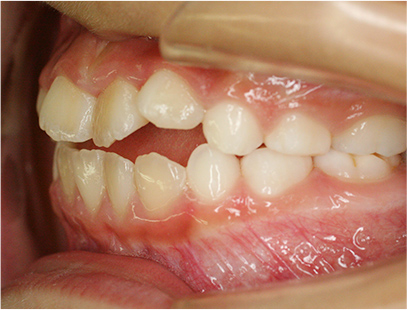

前歯の反対咬合

前歯部の反対咬合を主訴として来院されました。精査、診断の結果「前歯部の反対咬合」と診断されました。

治療前と治療後の写真

• 治療後

治療期間は患者様の努力とお母さまの協力が得られて5か月間で終了しました。